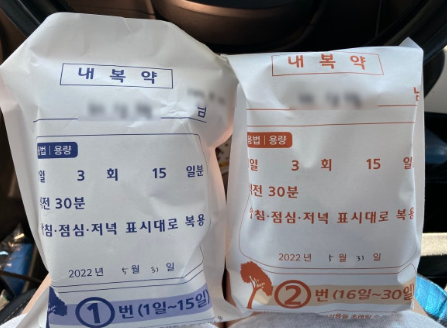

매체와의 인터뷰에서 나비는 “이런 크롭탑을 입어 본 게 몇 년 만인지 모르겠다. 출산 후에는 거의 임부복 수준의 펑퍼짐한 원피스만 입고 다녔었는데 20대 때 이후로 이런 옷을 입어 본 건 처음인 것 같다”라며 “출산을 하고 나서 살을 빼려고 이것저것 시도도 많이 했는데 매번 실패하면서 포기했었는데 전문가의 도움을 받아 15kg 감량 후 정말 나에게는 기적 같은 일이 일어난 것 같다”라며 다이어트에 성공한 소감을 전했다.

다이어트로 고민하는 사람들에게 나비씨는 장기간의 비만으로 호르몬에 변화가 생기고 여자들의 몸의 밸런스도 달라지다 보니 체중 감량도 중요하지만, 건강까지 생각하는 게 더 중요한 것 같다. 혼자서 하는 방법으로는 한계가 있고 그래서 다들 전문가의 도움을 받는 거 같다”라며 “옆에서 전문가의 도움을 받으니까 훨씬 빠르고 건강하게 다이어트를 할 수 있었다 다이어트를 고민하고 계신 분들은 혼자 하지 마시고 꼭 전문가의 도움을 받으시길 추천한다”라고 전했다.